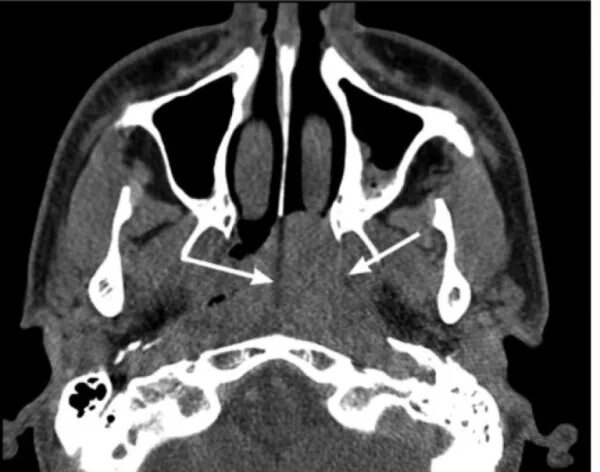

Миндалины на кт